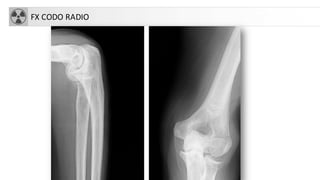

FX CODO RADIO

FRACTURA CODO

• Complejas a veces acompañadas de luxaciones

• Tipos:

– Supracondíleas: niños

– Trascondíleas: ancianos

– Intercondíleas: forma de T ó Y con separación de

cóndilos medial y lateral con la diáfisis

– Capitellum: fragmento libre en articulación

– Aisladas: cóndilo, tróclea, epitróclea, epicóndilo…

– Olécranon y apófisis coronoides

– Cabeza radio (30%)